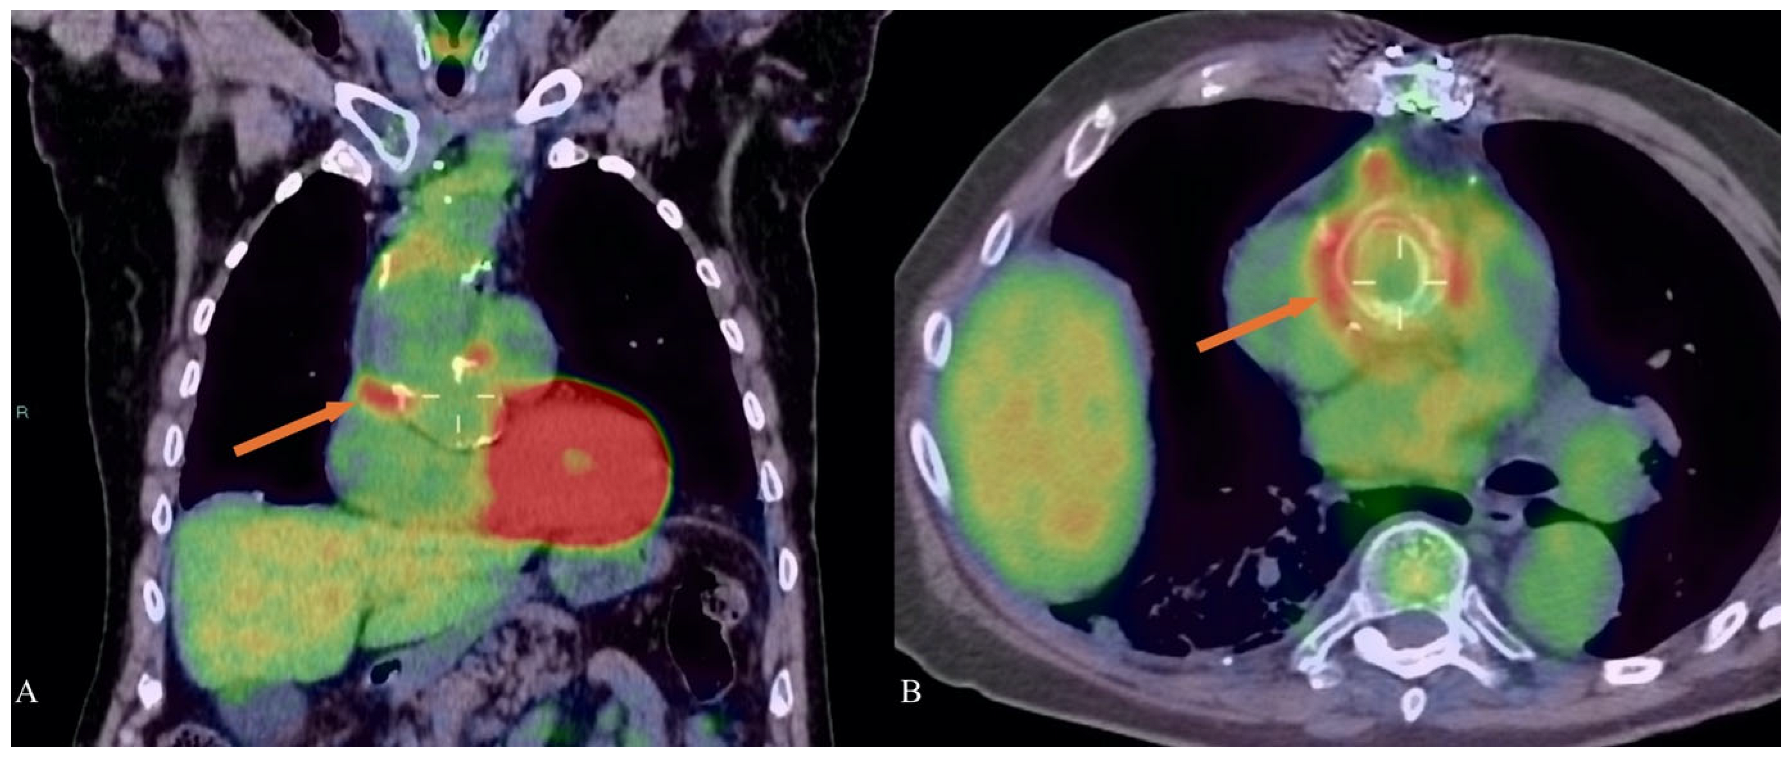

5. Nuclear Medicine and Marfan Syndrome

- Brili, S.V.; Gkotzamanis, V.; Kafouris, P.; Mystakidi, V.-C.; Sakalidis, A.; Antonopoulos, A.S.; Oikonomou, E.; Anagnostopoulos, C.; Tsioufis, K. The use of 18-Fluorodeoxyglucose positron emission and computed tomography in the evaluation of Marfan syndrome patients. JACC 2023, 81, 2017. [Google Scholar] [CrossRef]

| Nuclear Medicine | Use 18F-FDG PET/CT to detect aortic wall inflammation and complications such as chronic peri-aortitis or infections in prosthetic grafts. Utilize myocardial SPECT with 201Tl or 99mTc-based tracers for evaluating perfusion, viability, and cardiac pump function in Marfan cardiomyopathy, particularly when echocardiographic or CMR data are inconclusive. |